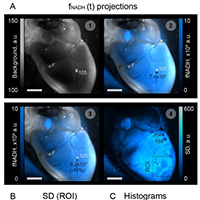

Коллектив исследователей Института биофизики будущего МФТИ и ИТМО разработал новый оптический метод, позволяющий с высокой точностью оценивать метаболические нарушения в живой сердечной ткани, вызванные недостатком кислорода (ишемией).

Изучать болезни сердца можно не только на целом органе, но и с помощью клеточных моделей. Например, культуры кардиомиоцитов, полученных из индуцированных плюрипотентных стволовых клеток (ИПСК).